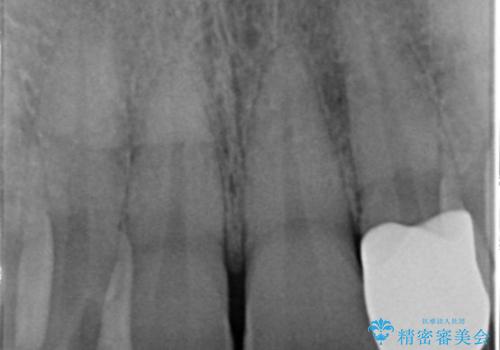

- 左の前歯が黒いとのことで来院。

1番目の歯は小さい虫歯があったのでプラスチックの樹脂で治療をしました(保険内)。

2番目の歯は二箇所虫歯があり、プラスチックの樹脂で治療するとつぎはぎみたいになってしまうので、

白い被せ物(ジルコニアクラウン)で治療しました。